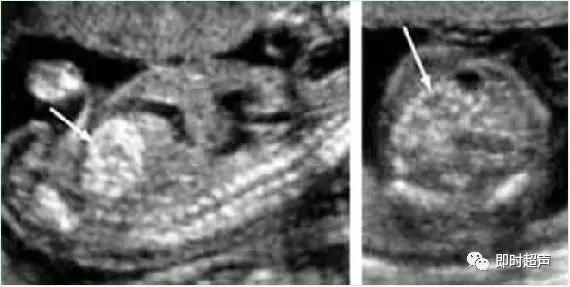

四、脉络丛囊肿(CPC)

脉络丛囊肿CPC 是指孕 14 ~ 28周经超声检查在胎儿侧脑室脉络丛内发现的散在的直径≥2mm 的小囊肿。

脉络丛是脑脊液分泌的重要场所,在胚胎发育的不同时期脉络丛的结构发生较大变化,间充质基质由稀薄逐渐浓缩,脉络丛内的毛细血管发生血管瘤样改变,包裹一部分脑脊液形成脉络丛囊肿。

✔ CPC发生率1%-2%,正常胎儿可一过性出现。

✔ 声像图为在均质强回声的脉络膜丛内见到圆形或椭圆形无回声结构,多为3-5mm大小。

✔ 单纯CPC中染色体异常的机率在1%-2.4%。

✔ 妊娠26-28周左右95%以上的CPC逐渐消失。

✔ 大约有1-3%的正常人群中在中期妊娠的超声检查中可发现有CPC。有建议5mm以下不报告。

✔ 如果囊肿小于1cm或越来越小,染色体异常可能性小。

✔ CPC本身不会造成胎儿发育异常,包括智力障碍、脑瘫和发育迟缓等。

✔ 囊肿大于 1 cm 时,约 1% ~2%有胎儿染色体异常,这些胎儿大部分都有另外的畸形。以 18 、21-三常见。

✔ 胎儿脉络丛囊肿作为产前超声诊断中的超声标记之一,可以提示胎儿染色体异常的风险性。

✔ 囊肿较大或胎儿合并其他畸形时应做胎儿染色体检查。